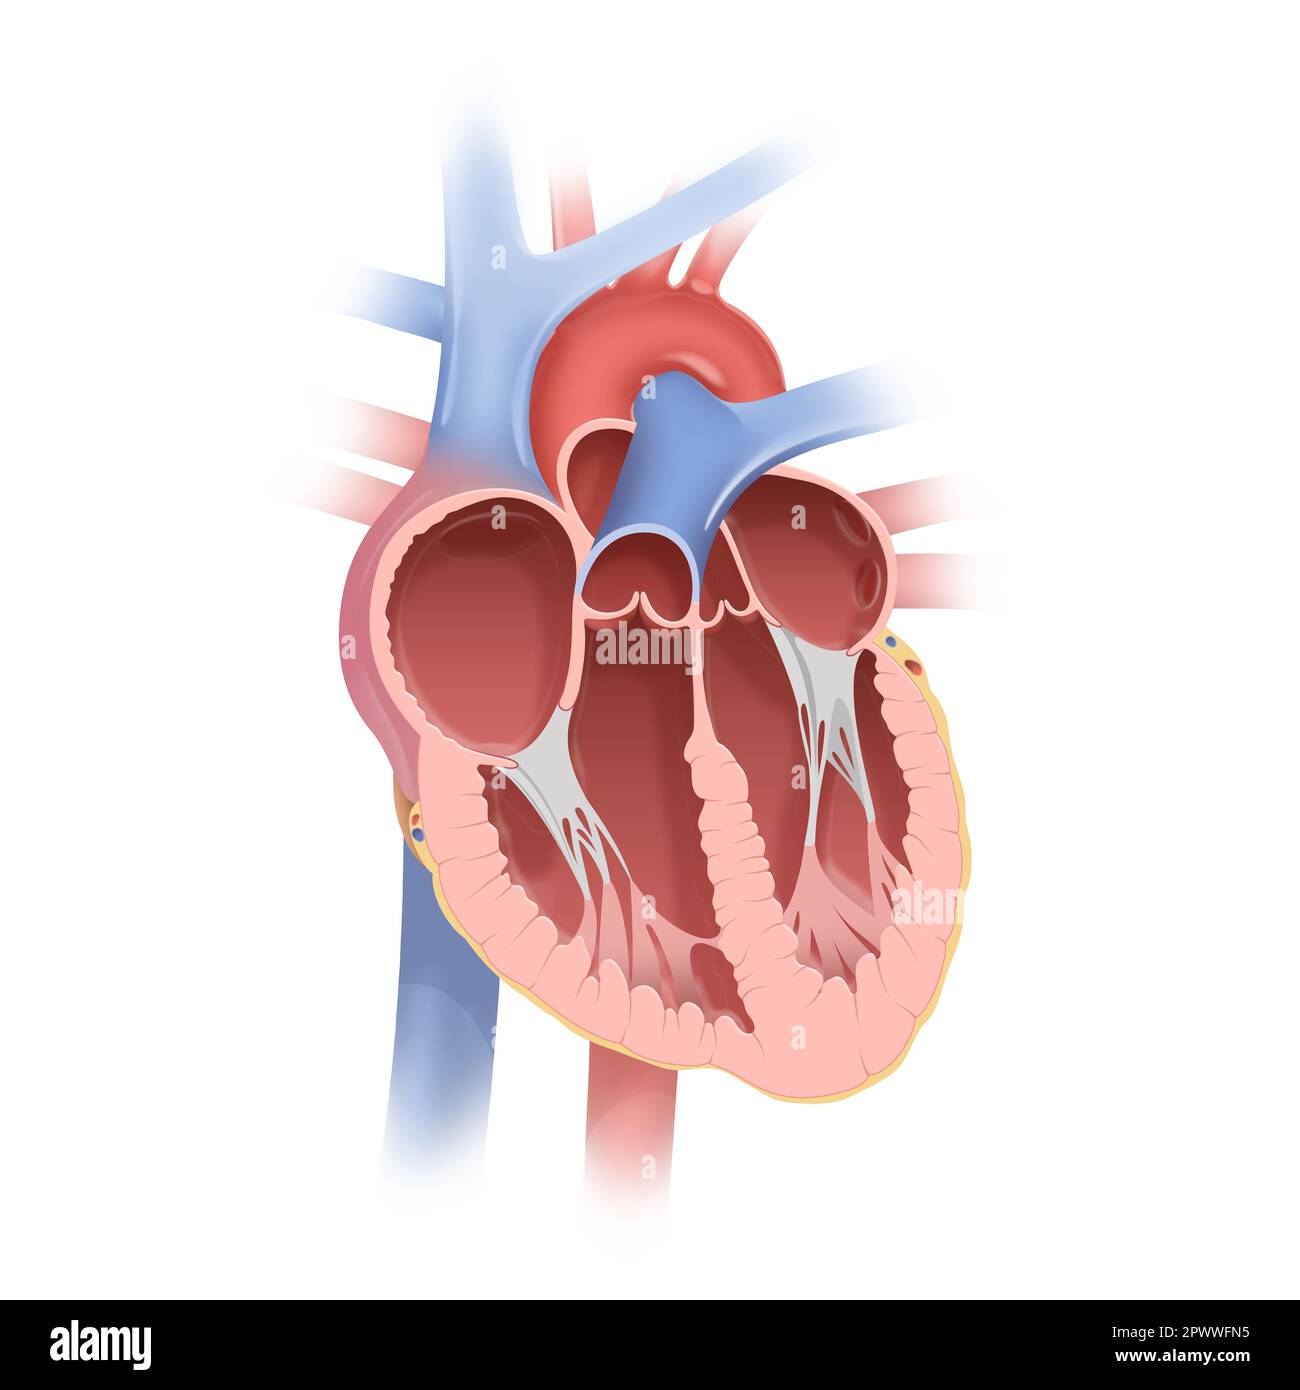

Anatomy of the Human Heart Stock Photohttps://www.alamy.com/image-license-details/?v=1https://www.alamy.com/anatomy-of-the-human-heart-image549448961.html

Anatomy of the Human Heart Stock Photohttps://www.alamy.com/image-license-details/?v=1https://www.alamy.com/anatomy-of-the-human-heart-image549448961.htmlRF2PWWFN5–Anatomy of the Human Heart